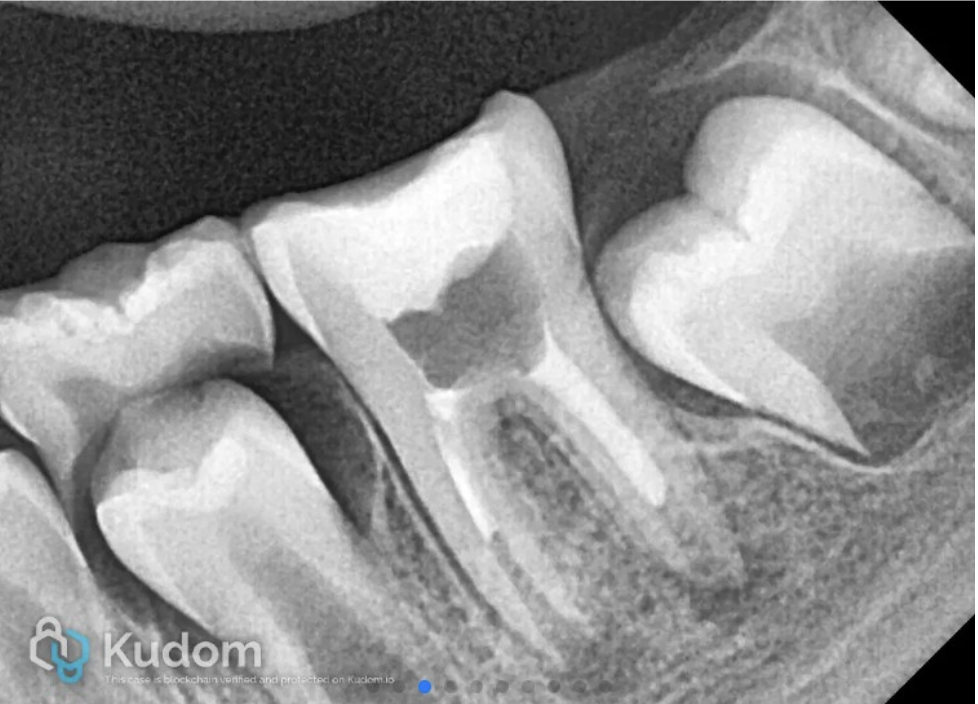

Follow-up IOPA at 24 months

Follow-up radiograph at 30 months showed resolution of periapical lesion, and completion of root formation and establishment of lamina dura.